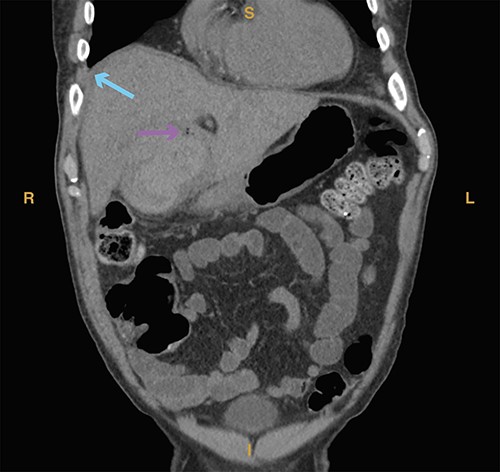

A 23-year-old woman with a past medical history of autoimmune hepatitis with ascites on azathioprine and prednisone presented from an outside hospital with 24-hour acute onset of worsening right upper quadrant pain and mild nausea. Patient’s model for end-stage liver disease score based on an INR value from 3 months prior is 14. Prior to being transferred to our emergency department, the patient was hypotensive (systolic blood pressure of 90 mm Hg) and given crystalloid resuscitation. Initial workup revealed a hemoglobin of 8.9 g/dl, a hematocrit of 25.8%, elevated lactic acid to 2.7 mmol/l (normal range 0.3–1.9 mmol/l) and elevated total bilirubin of 2.4 mg/dl (normal range 0.3–1.2 mg/dl). Computed tomography of the abdomen and pelvis revealed significant hemoperitoneum with suspected gallbladder perforation, as well as small calculi in the gallbladder neck (Fig. 5).

Computed tomography imaging from Case 3 showing significant hemoperitoneum (cyan arrow). Present in the figure, the letters S, L, I and R denote superior, left, inferior and right respectively.

On exam, the patient was in mild discomfort with some pain localized to the right upper quadrant without rebound or guarding. However, in the setting hemodynamic instability for which the patient received 2 units of packed red blood cells in the emergency department, downtrending hemoglobin and radiographic findings of hemoperitoneum, the decision was made for urgent surgical intervention despite poor liver reserve due to patient’s Child-Pugh class B cirrhosis.